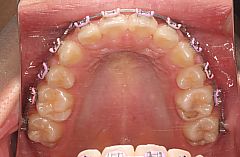

上顎前突治療例9(上顎両側第一小臼歯抜歯、唇側の矯正装置)

上顎左側中切歯の唇側傾斜を認めました。下顎前歯が廷出しており(スピーの湾曲が強い)、過蓋咬合(咬み合せが深いこと)を呈していました。また、大臼歯関係はAngleⅡ級でした(下顎第一大臼歯が上顎第一大臼歯に対して相対的に半咬頭以上後方にありました。これは、本症例が前歯の傾きだけの問題ではなく、上顎歯列全体として下顎歯列に対して前方位にあることを示しています≒骨格性の上顎前突症)。

治療方針:上顎両側第一小臼歯を抜歯し、その抜歯スペースを利用して上顎前歯部叢生の改善と上顎前歯の後方移動を行うことにしました。

治療器具:マルチブラケット装置(メタルブラケット)